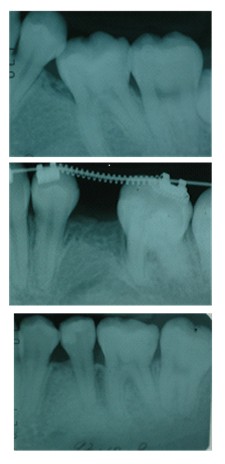

對於”牙周病”這個名詞,大部分的人聽說過,但是究竟牙周病是什麼樣的疾病,卻一無所知。簡單的說”牙周病”是牙齒周圍的組織發炎,並且受到破壞的疾病。那麼牙齒周圍的組織指的又是什麼呢?牙周組織包括了牙齦(牙肉)牙齦下的齒槽骨、牙齦最下方的牙骨質與牙跟之間的牙周膜。因此牙周病包括牙齦炎與牙周炎。